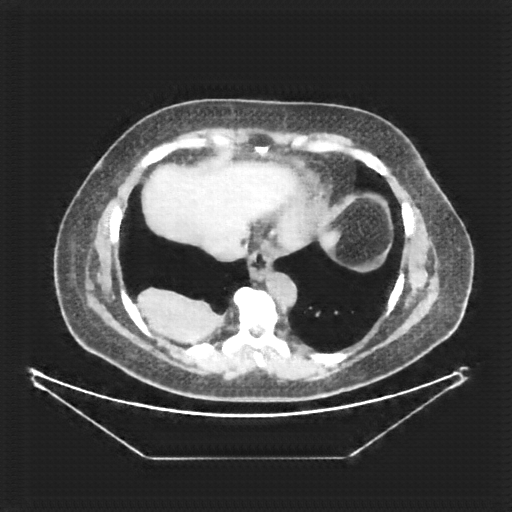

Original VENOUS CT scan

Full window (WL 1023.5, WW 4095 β†’ Low βˆ’1024, High +3071)

Lung window (WL -600, WW 1500 β†’ Low βˆ’1350, High +150)

Mediastinum window (WL 40, WW 400 β†’ Low βˆ’160, High +240)